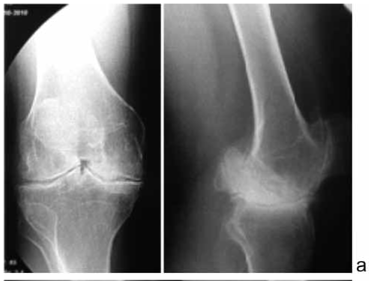

Всем пациентам при поступлении в стационар в первую очередь проведено рентгенологическое исследование коленного сустава с использованием цифровой системы, исследование проводилось до и после операции эндопротезирования (рис. 1).

Для оценки тяжести поражений суставов у больных гемофилией мы придерживались клинико-рентгенологической классификации Э.З. Новиковой [4], в которой различают четыре стадии гемофилического остеоартроза.

В I стадии увеличен объём сустава за счёт кровоизлияния. В «холодном» периоде функция сустава не нарушена, но рентгенологически может обнаруживаться утолщение и уплотнение суставной капсулы, а также умеренный остеопороз суставных концов.

Во II стадии определяются характерные изменения в субхондральном слое эпифизов - краевые узуры, образование субхондральных кист. Визуализируются не большие краевые дефекты на боковых поверхностях суставных концов от локального воздействия гематом. Остеопороз прогрессирует. Объём движений в суставе уменьшен.

В III стадии сустав значительно увеличен, дефигурирован, имеется гипотрофия мышц. Амплитуда движений резко ограничена.

Рентгенологически определяется деформация суставных концов, разрушение субхондрального слоя, сужение суставной щели. Имеются краевые костные разрастания, выражен остеопороз.

В IV стадии функция сустава полностью утрачивается, суставная щель резко сужена или отсутствует. Отмечается выраженный склероз субхондрального слоя кости и кистовидная перестройка эпифизов.

Согласно данной классификации, по данным рентгенографии из 104 обследованных коленных суставов в 27 (26 %) патологии не выявили (хотя пациенты жаловались на боли в суставах), I рентгенологическая стадия диагностирована в 6 (5,8 %) коленных суставах, II стадия – в 7 (6,7 %), рентгенпризнаки артроза III стадии выявлены в 39 (37,5 %), IV стадии – в 25 (24 %) суставах. У всех 9 больных с жалобами на боли в тазобедренном суставе рентгенологическая картина соответствовала III-IV стадии артроза, с грубым нарушением функции суставов.